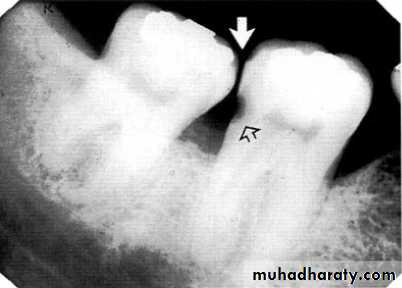

3.Furcation involvements:

Bone loss in the furcation area of the roots which is evidence of advanced disease in multirooted

teeth.

Initially seen as widening of the PL space at the crest of

the furcation . As lesion progresses, the bone

loss progresses apically.

Mild/moderate/sever.